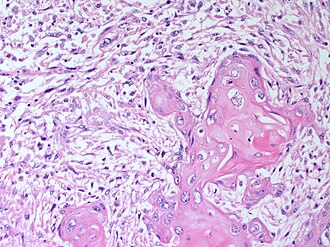

Metaplastic breast carcinoma. H&E stain.

LM either (1) or (2): (1) malignant mesenchymal elements - either: (a) spindle cells or (b) osseous, chondroid or rhabdoid differentiation, (2) malignant squamous component - non-skin